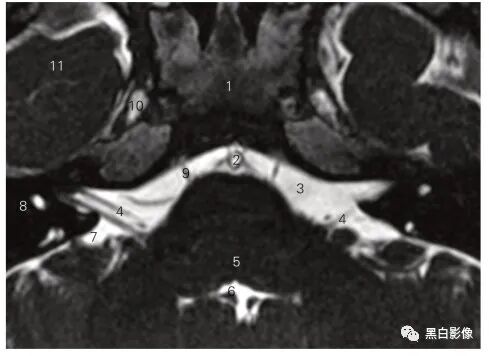

图5-1 经嗅球的冠状断层MR T1加权图像

1 嗅束沟 olfactory sulcus 2 嗅球 olfactory bulb

3 内直肌 medial rectus 4 鼻中隔 nasal septum

5 下直肌 inferior rectus 6 下鼻道 inferior nasal meatus

7 下鼻甲 inferior nasal concha 8 上颌窦 maxilary sinus

9 筛窦 ethmoid sinus 10 视神经 optic nerve

11 嗅池 olfactory cistern 12 眶回 orbital gyrus

13 直回 gyrus rectus 14 额叶 frontal lobe

15 大脑镰 cerebral falx